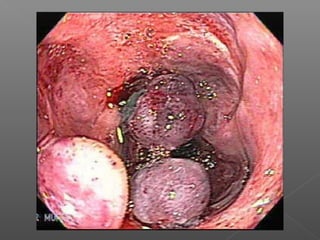

Clasificación de várices esofágicas

Grado I Grado II Grado III

Sociedad Japonesa para el estudio de la hipertensión portal.

 Grado 1: cordones que desaparecn con la

insuflación.

 Grado 2: cordones que se aplanan parcialmente

con la insuflación.

 Grado 3: ocupan menos del 50% de la luz.

 Grado 4: ocupan más de 50% de la luz.